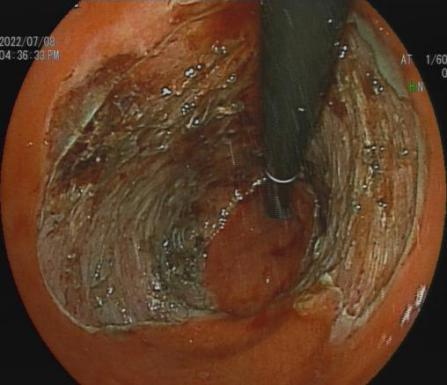

三、早期消化道肿瘤ESD技术

内镜下粘膜剥离术(ESD),具有超级微创、安全性高、住院时间短及费用低等优势。

直肠巨大绒毛状腺瘤 内镜下粘膜剥离过程

粘膜剥离术后创面 剥离的巨大腺瘤